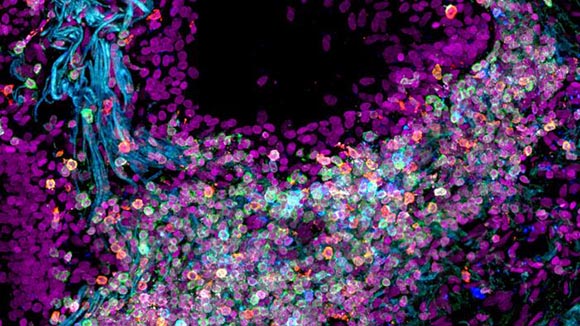

אחת מפריצות הדרך הייתה האפשרות לרצף גם מולקולות RNA מדגימות התאים. תאי ריאה מתוך אטלס התאים | Nathan Richoz University of Cambridge